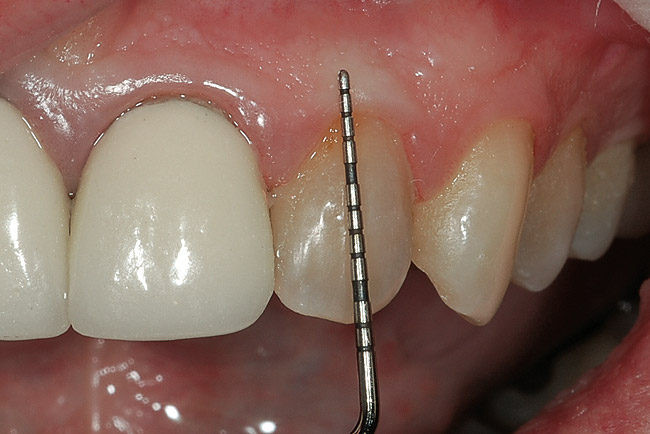

The Initial Examination

The first and most important consideration is to determine the cause of the tooth discoloration. A clinical examination is conducted, which includes evaluation of the color of the teeth and the adjacent gingiva (Figure 1). Additionally, transillumination, radiographs, and pulp testing may be appropriate. Radiographs should always be taken of a single dark tooth, as teeth can undergo pulpal necrosis without any other symptom than becoming dark (Figure 2). From this examination, the determination is made of whether the tooth is vital or not. A vital tooth may be darker due to trauma and resultant bleeding into the dental tubules without loss of vitality. Vital teeth may also discolor from internal or external resorption, calcific metamorphosis, as well as decay or leaking restorations on the proximal or lingual surfaces. A non-vital tooth may have become darker from the same reasons as a vital tooth, but also have experienced pulpal death. A tooth that has received endodontic treatment may also later darken, especially if there is a poor seal of the endodontic access opening (Figure 3).

Figure 1  A clinical examination demonstrates a single, very dark lateral incisor and a moderately dark central incisor with a crown on the adjacent central incisor and several dark gingival areas.

Figure 1